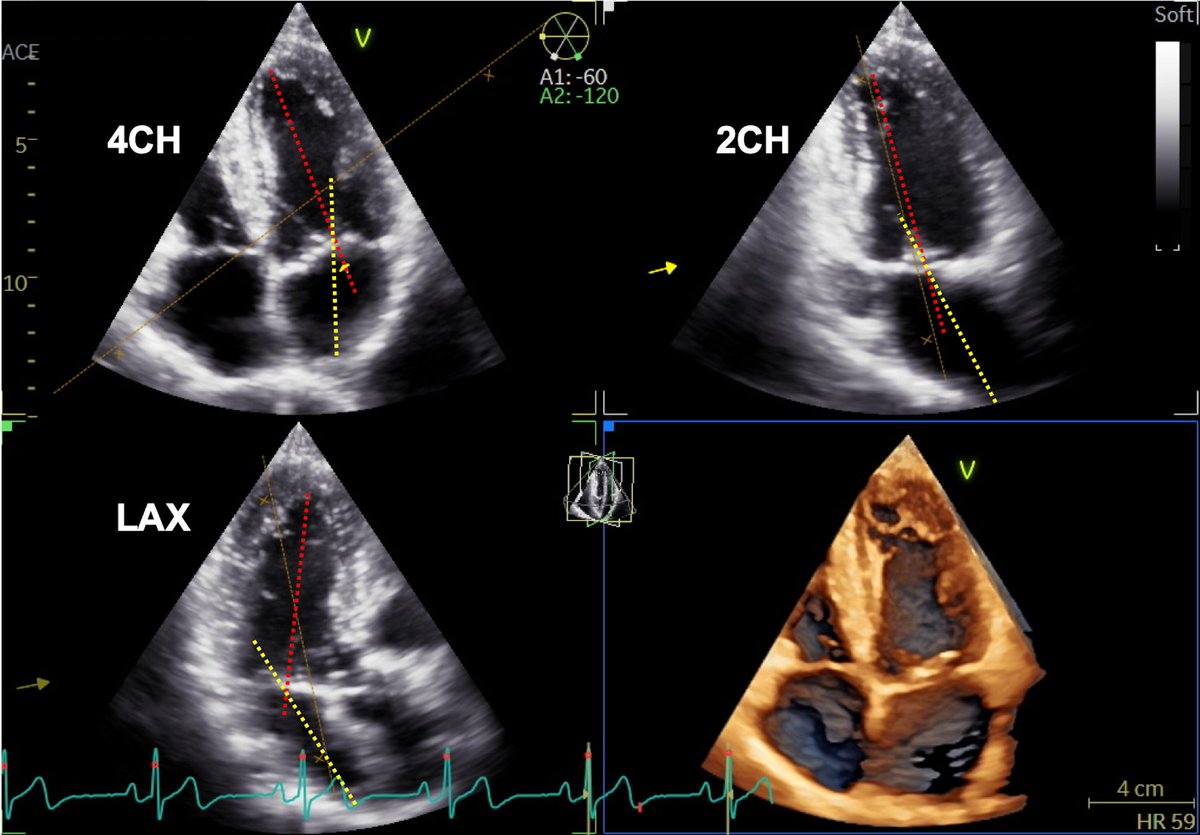

For long-axis 2-chamber view (2Ch) images, the left atrium (LA) endocardial border was traced. 3 axis G-sensors with adjustable sensitivity settings The DR590W-2CH is a dual-channel dashcam that records both front and back of your vehicle in Full HD 1080p. Unfortunately I didn't get to test it out before buying it.

Reference Image Showing Four Chamber 4ch Two Chamber 2ch Download Scientific Diagram

Luigi على تويتر This Is Another Important Concept We Have Realized Using 3decho Lv And La Long Axes Are Never Coaxial To Have Accurate La Volumes You Cannot Use The Apical Views